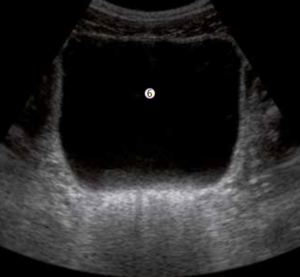

Per fare diagnosi è importante la storia clinica del paziente, l’esame neurologico e gli esami strumentali e biologici: risonanza magnetica, potenziali evocati visivi (esame che indaga l’integrità del nervo ottico e delle vie di conduzione), esami del sangue e del liquido cerebrospinale.